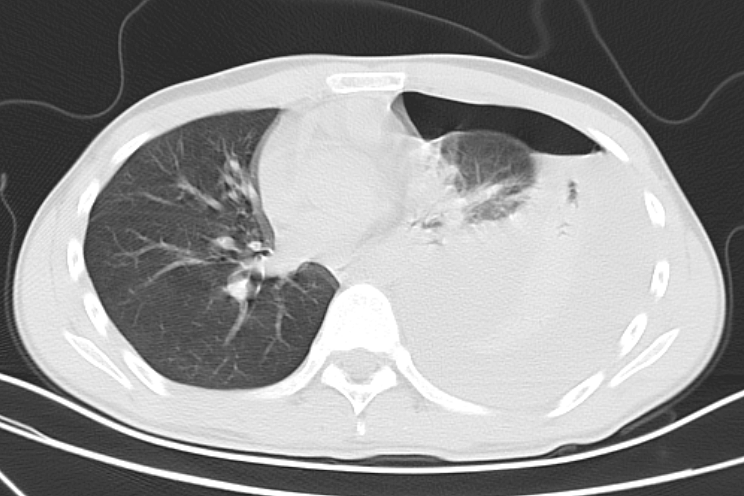

小陈的影像CT检查提示,左侧肺部压缩90%,相当于影像片上,左肺有九成大小“消失了”,他随即被收住入院。